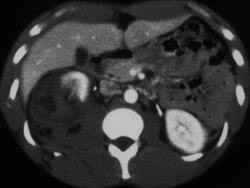

Shock Bowel and Hypoperfusion Due to IVC Injury